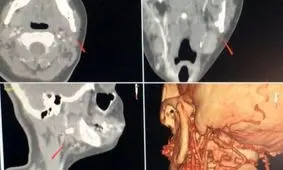

هنوز مشخص نیست که در دو دهه پیش چه اتفاقی افتاده بود که یک مرد میانسال چینی فکر کرد که بلعیدن یک چراغ قوه می تواند…